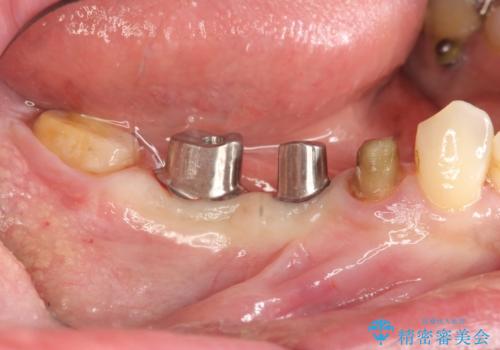

設計に無理のある長期的に良好な状態が保てるとは思えないブリッジを除去し、インプラントを用いた補綴計画を立てます。

- 80万円(ストローマンインプラント×2・チタンカスタムアバットメント×2・ジルコニアクラウン×4)費用は治療当時の料金となります